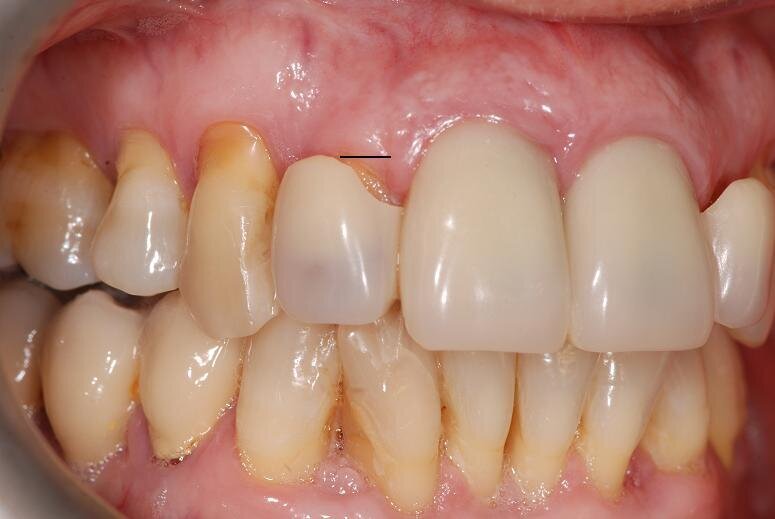

Dopo alcuni mesi, declinando gli inviti da parte dello studio a riprendere le cure, si rivolge ad altro professionista, sottoponendosi ad un nuovo trattamento implanto-protesico e all’estrazioni dei due incisivi centrali residui con inserimento di quattro impianti in posizione 1.2 - 1.1 - 2.1 e 2.2. A distanza di circa due anni, la paziente cita in giudizio il primo professionista e chiede il risarcimento dei “danni subiti” dal trattamento implantare “fallito”; contestava inoltre i trattamenti protesici effettuati quattordici anni prima!